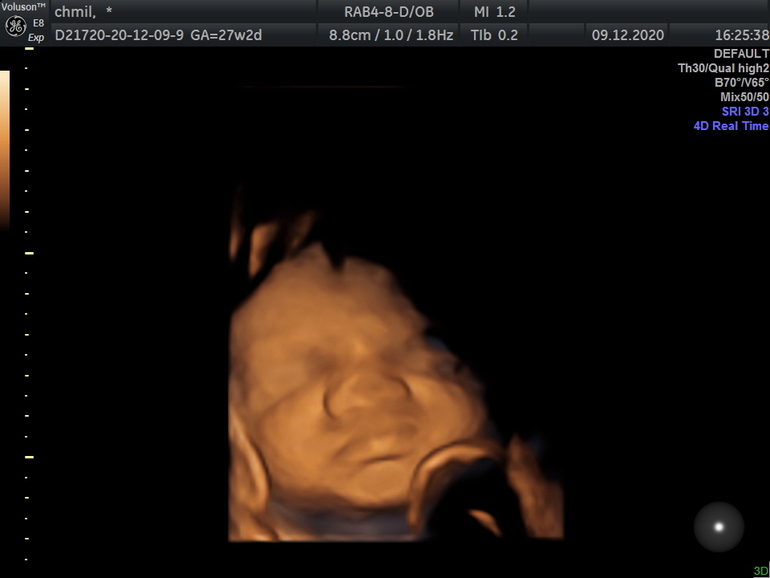

Короче поехали мы на узи, врач была просто душка, очень ласково разговаривала с малышом, умилялась вместе с нами, всё-всё коммментировала и весь процесс можно было наблюдать на большом экране. Ещё показала детеныша в 4д и скинула фотки на флешку😍! Правда он опять сосал палец и почти все время закрывал руками лицо, но потом всё же сделал одолжение и разрешил посмотреть на него как следует пару минут))

Пришли к выводу, что когда он спокоен - похож на меня, а когда корчит морды и недоволен - вылитый муж 🤣. Для сравнения, вот моё первое фото:

Параметры все в норме, шейку померили через живот, получилось 30 мм (на 2м скрининге трансвагинально была 40, поэтому думаю что все же не 30, а чуть длиннее, но если нет- всё равно это норма). Ребенок весит аж ~1130г, опережает в развитии на неделю, если считать по месячным, а учитывая, что у меня была поздняя овуляция, то даже на две недели опережает. В целом показатели соответствуют 28,2 нед.😲